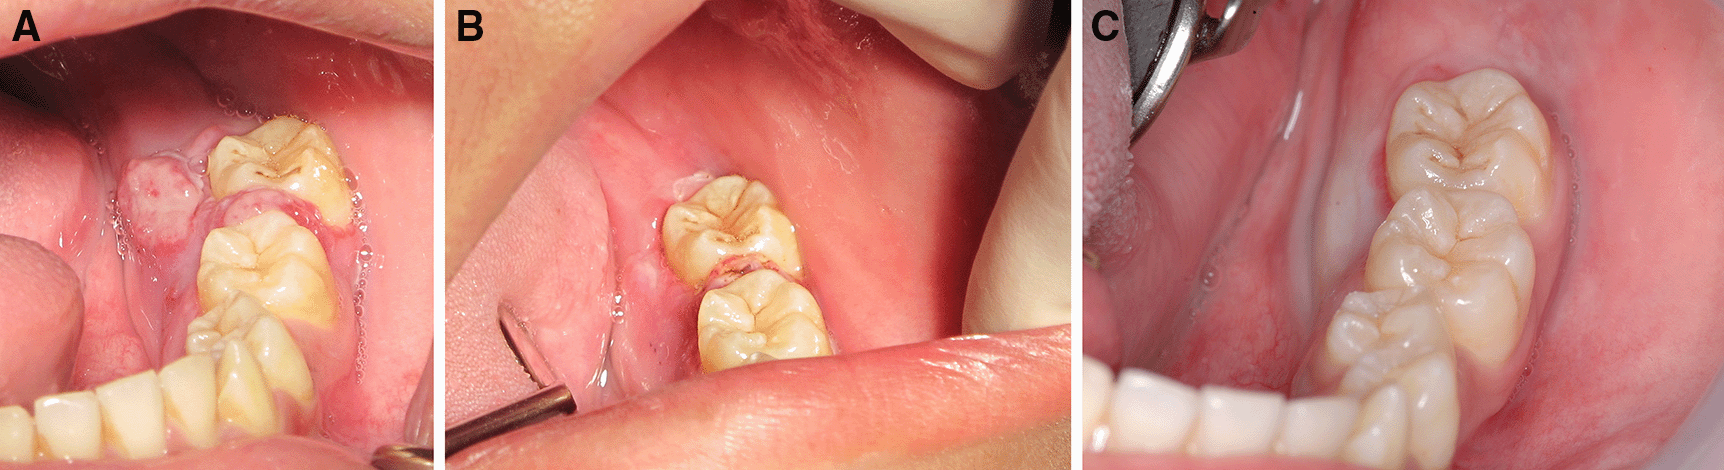

The patient was invited to have appointments for interstitial-intralesional laser therapy as previously described every two to three weeks. The remission of the pyogenic granuloma was observed, as shown in Figure 6A, B and C.

A. 2 weeks after the first therapy.

B. 2 weeks after the second therapy.

C. 3 weeks after the third therapy.